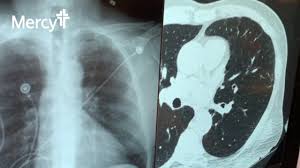

Lung Cancer Screening Lose Dose Ct Could Be Key To Survival

Lung Cancer Screening Lose Dose Ct Could Be Key To Survival from hjg1712ej6y3pw6xssstoglk-wpengine.netdna-ssl.com

Ldct scans can help find abnormal areas in the lungs that may be cancer ldc. Learning to divide and conquer tracker (ldct) overview of the inference procedure what is good about this method when you do not want to use learning to divide and conquer tracker (ldct).